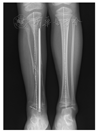

按照上述标准,共有41例患儿纳入本研究,其中男17例,女24例。收集数据包括手术开始年龄、手术时间、术中出血量、住院时间、术前胫距角和术后胫距角。所有患儿拍摄双下肢负重全长X线片,通过测量胫距角评估踝外翻程度。由于CPT患儿常伴有胫骨弯曲,测量胫距角选择胫骨髁间嵴中心与踝关节间隙水平的中点连线与距骨穹窿关节面的夹角(图1)。胫距角正常范围为80°~90°,10°以内的外翻可通过后足关节活动来尽量纠正[18,19]。

41例患儿术后随访至少16个月,平均随访时间为36个月。平均手术时间24 min,术中出血量平均7.5 ml,平均住院时间4.4 d。所有患儿术前胫距角为(73.9±4.4)°,去除内固定时胫距角为(86.9±4.7)°,末次随访时胫距角为(84.6±5.5)°(图3)。所有患儿去除内固定时平均矫形率为0.69°/月。"U"形钉治疗踝外翻畸形典型病例如图4、图5所示。所有患儿术后未出现螺钉脱出、骨髓炎、伤口感染等严重并发症,术后踝关节活动良好,无关节僵硬。患儿内固定拆除后未出现骺板损伤等情况。